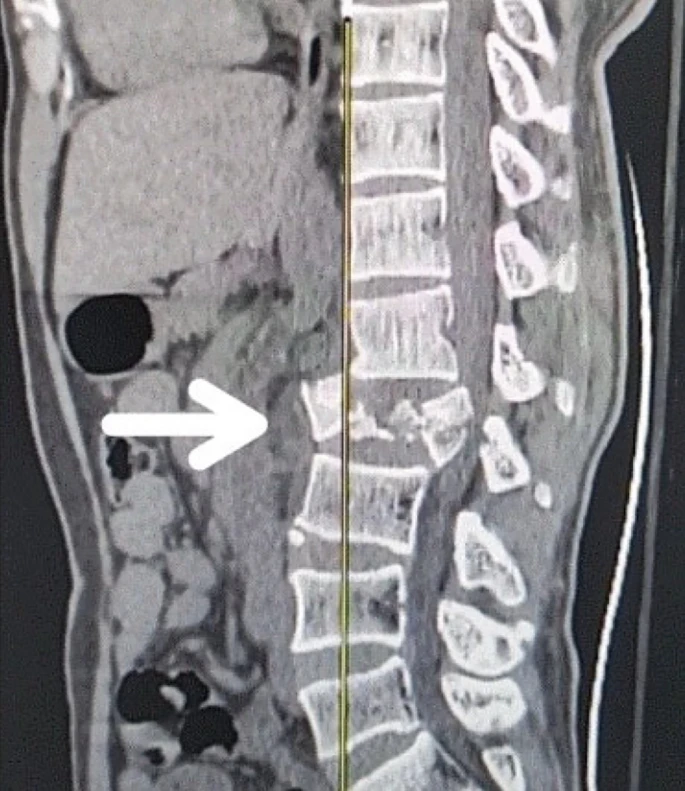

創(chuàng )傷性脊髓損傷是由于脊柱受到突然的強力撞擊,導致椎骨骨折、脫臼、擠壓或壓縮(圖1)。主要原因包括機動(dòng)車(chē)事故,其中汽車(chē)和摩托車(chē)碰撞占每年新增脊髓損傷病例的近一半。跌倒,尤其是65歲及以上人群的跌倒,是造成脊髓損傷的重要原因,約占60%。體育活動(dòng),例如沖擊性運動(dòng)和淺水潛水,約占此類(lèi)損傷的10%。

圖1:X射線(xiàn)圖像顯示脊髓損傷,椎骨骨折和移位,如白色箭頭所示